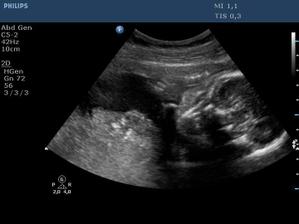

Ultrazvuk miminka - 24 týden

Z "menší protekce" u pana primáře Radiodiagnostického oddělení jsme mohli na soukromou "špionáž" naší krásné holčičky... (Pan doktor je už třetí, kdo hádá holčičku a po pravdě s tím přístrojem, co má k dispozici, bylo naprosto zřetelně vidět, že tam žádný pytlík není! :o)) Natočil nám i několik videí, kde ta naše šibalka zívala a dvakrát na nás dokonce vyplazovala jazyk. ;o)